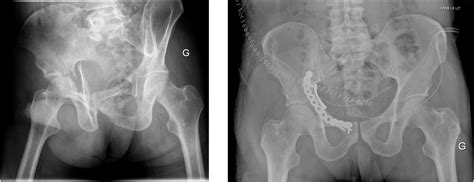

Understand the complexities of fractures of the acetabulum with our expert guide. We cover critical pelvic trauma diagnosis, advanced surgical stabilization techniques, and essential post-operative rehabilitation protocols. Learn how orthopedic specialists manage these complex hip joint injuries, optimize recovery outcomes, and address potential long-term complications following severe pelvic ring damage. Ensure optimal patient care with evidence-based treatment insights.

TitleAcetabulum fractures in the elderly, reconstruction or replacement ? - Journal of Clinical ...